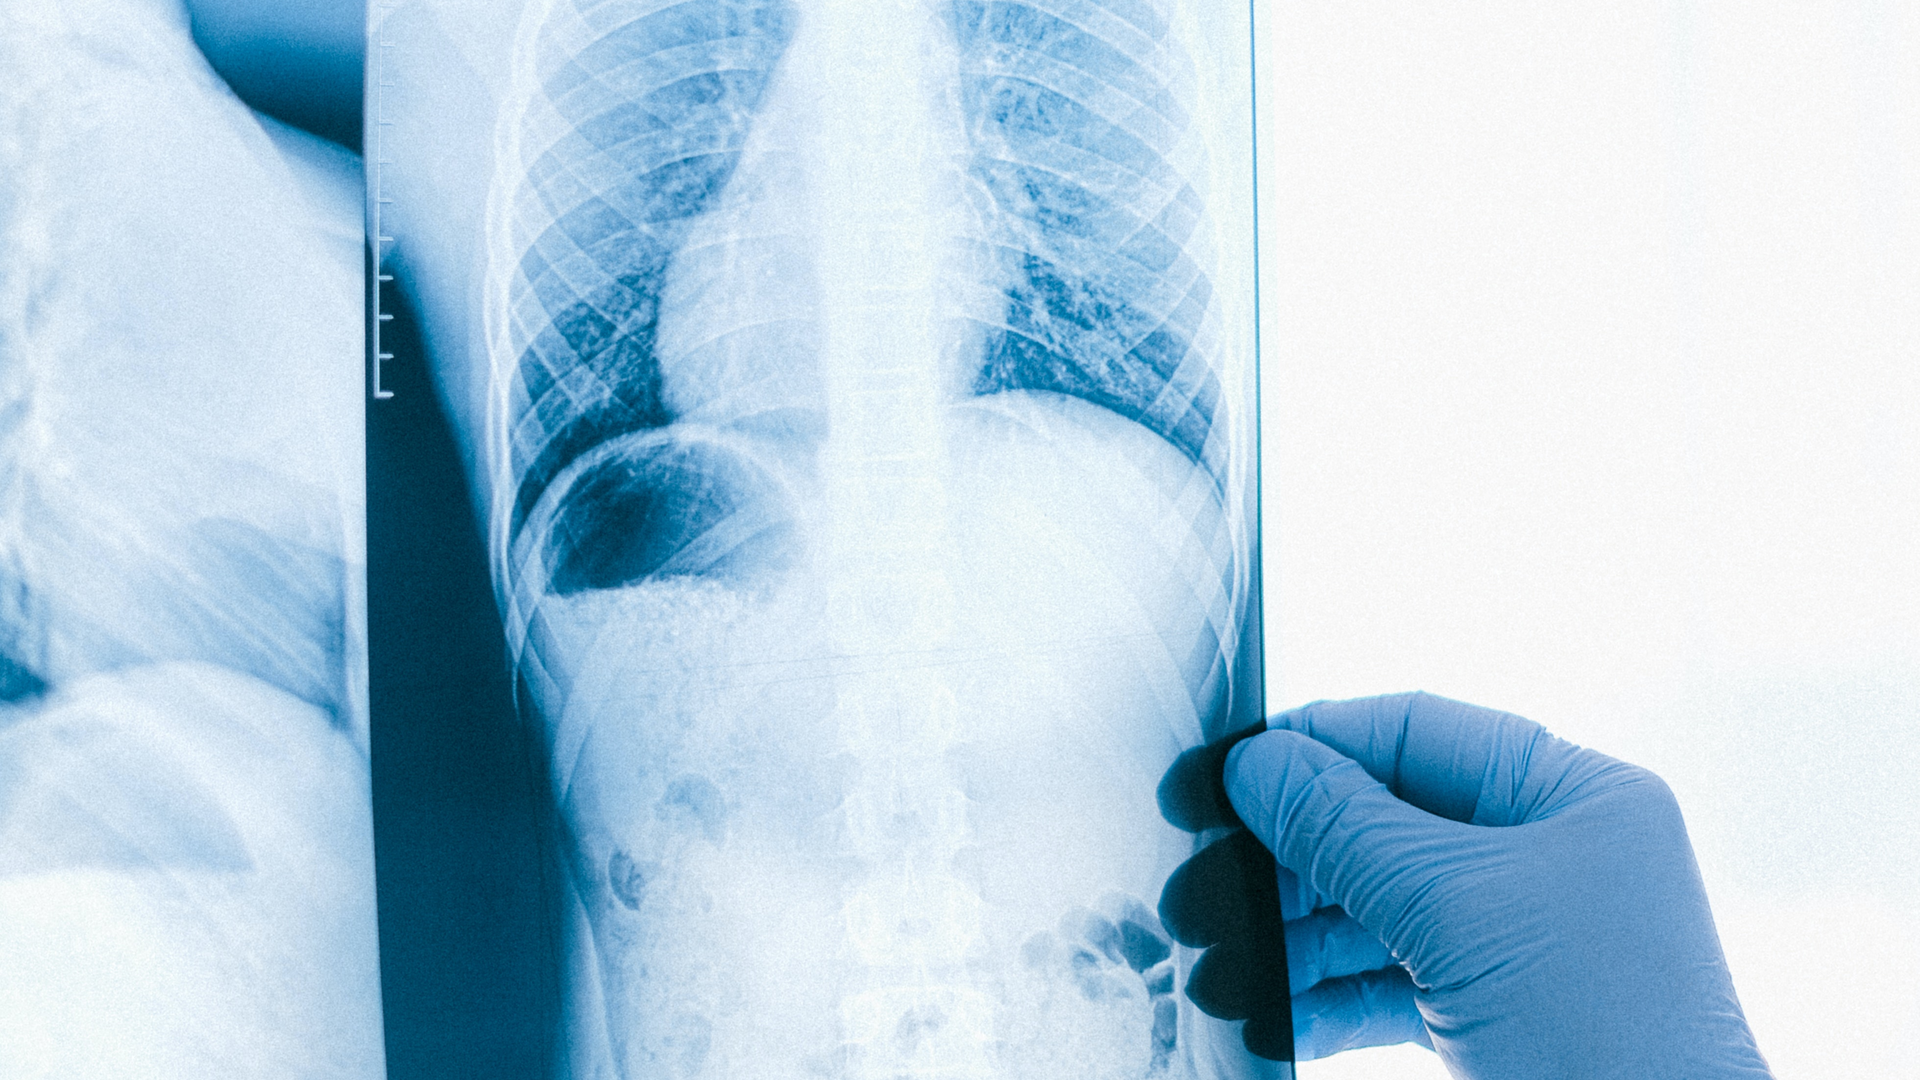

People who presented with three or more symptoms were more likely to be diagnosed more promptly than those presenting with fewer symptoms—likely because the presence of more symptoms raised physician suspicion. The use of chest X-rays or CT scans to image the lungs, the use of a molecular TB test called nucleic acid amplification, and receiving care from a TB specialist, all expedited diagnoses.

The bottom line for clinicians, Farhat said, is to err on the side of over-testing: The risk of missing TB far outweighs any possible downsides of ordering a fairly inexpensive molecular test or an X-ray to rule out TB disease.

“If you have a patient with cough, fever, shortness of breath, especially if they were born abroad or are an older individual, then you should be ordering a chest X-ray early and, if abnormalities are seen, a TB nucleic acid amplification test,” she said. “Yes, these are non-specific symptoms, but the key is to think about it TB as a possibility and to remember that it is still present in the United States.”